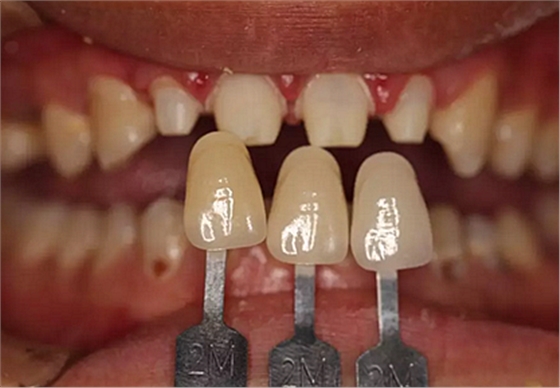

兩周后,主人帶我們往醫(yī)院拆線,取模,比色,為我們重新量身定制了一套堅固的“外套”。